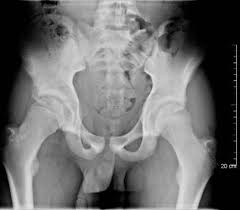

Hip pain in children is always a potentially serious and needs urgent assessment. Call 999 and ask for an ambulance. They are serious injuries that most often occur in people aged 65 and older. I am 15 and did it to my hip/ upper pelvic bone. They usually happen when a bone is moving one way, and a tendon or ligament is suddenly pulled the opposite way.

Acute Avulsion Of The Iliac Crest Apophysis In An Adolescent Indoor Soccer from www.jbsr.be I am 15 and did it to my hip/ upper pelvic bone. An avulsion fracture is a fracture in which part of the bone breaks off from the rest of the bone. When the fracture happens, the tendon or these fractures most often affect bones in the elbow, hip, and ankle. What causes a hip fracture? There are numerous sites at which these occur. Hip pain in children is always a potentially serious and needs urgent assessment. Teenagers are more likely to have this injury than younger children. Hip fractures can limit mobility and independence.

Pain in the hip area may be referred from the knee joint or from structures in the inguinal canal, testis (including torsion) and lower abdomen, or from the lower back. Teenagers are more likely to have this injury than younger children. The causes of hip fracture are very different in young and elderly patients. Other causes include cancer and injury. Hip fracture occurs in approximately 341,000 persons in the united states each year. Read about causes, treatment options, available mobility devices, tips for recovery, and more. This happens when a muscle or tendon connected to the hip bone suddenly tightens so hard that it pulls off part of the bone. In acute avulsion fractures, there is usually a clear preceding traumatic incident. A hip fracture is a break in the bones of your hip. A hip fracture is a common injury, especially in people with osteoporosis. I was doing high jump and twisted my body and in the process my muscle ripped my growth bone off. A broken hip in older people is often partly the result of weakening bones from osteoporosis. This most commonly occurs at the ischial tuberosity where the hamstrings attach, or the iliac pain at the bony part on the front of the hip may be an anterior superior iliac spine avulsion fracture.